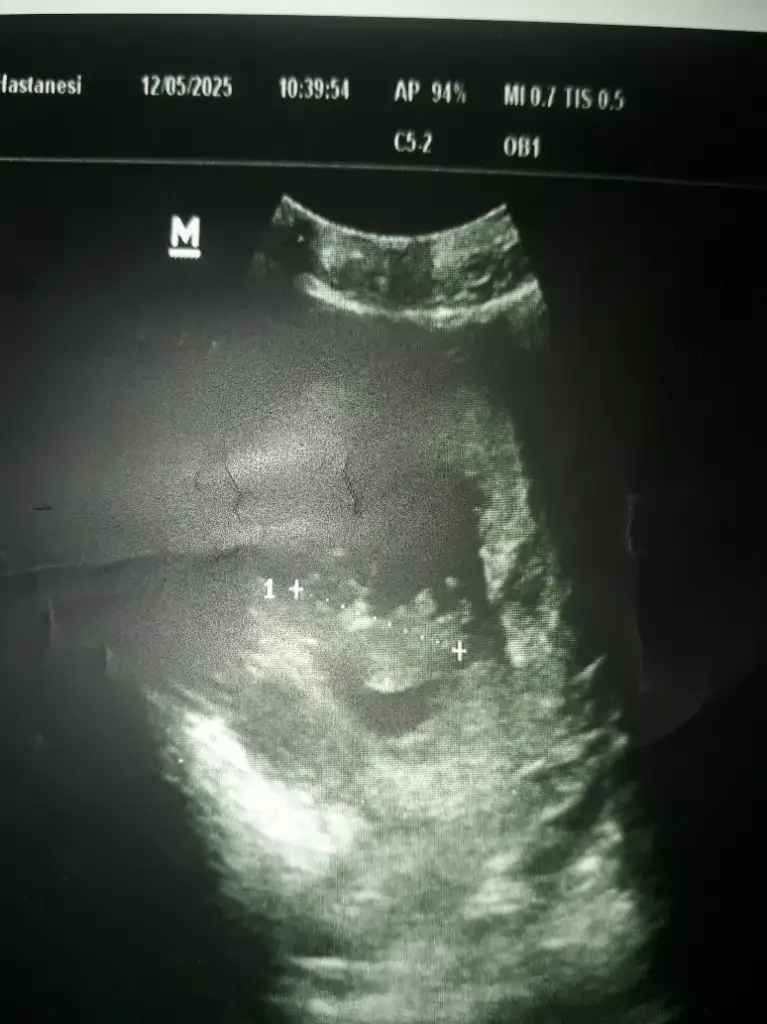

Kızlar benimki ne sizce doktor erkeğe benzetti ama kesin konuşmadı 🙁 12+2

IMG_0614.webp

Eklentiler

• IMG_0572.webp

IMG_0572.webp

24,4 KB · Görüntüleme: 39